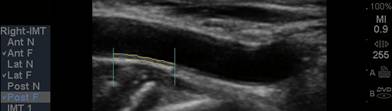

The CIMT procedure is

simple. An ultrasound study is carried out of the carotid arteries in your

neck. A specialized software program is used to precisely measure the mean and

maximum IMT. Standard carotid ultrasound is looking for “flow-limiting”

stenoses, narrowings that could be addressed surgically. This is not what we

are interested in with CIMT testing - we will be measuring soft plaque

accumulation in non-overtly diseased vessel segments (if plaque is identified we

measure the CIMT at an adjacent, normal appearing segment). While the presence

of plaque obviously has significance, it is the IMT parameter that best predicts

the presence and severity of atherosclerotic vascular disease elsewhere in your

body, it’s risk of progression, and your risk of sustaining an atherosclerotic

event (think of IMT as the “staging ground” for obstructive plaque – the higher

the IMT, the greater the rate of IMT progression, the more rapidly will large,

obstructive plaques form). Over 2,000 studies (go to www.pubmed.gov and enter

Carotid IMT) document the link between CIMT and current risk, and an even more

powerful relationship between the rate of change in CIMT and future risk. We

will use CIMT to help us decide who should be treated with preventive measures

and how aggressive our efforts should be. We will use the rate of change of

CIMT to gauge the success of the regimens that we construct for you.